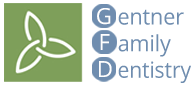

Patient Has Dental Crown Placed

This patient had a crown on #12 done by Dr Gentner along with adding it to fit their partial - Great work